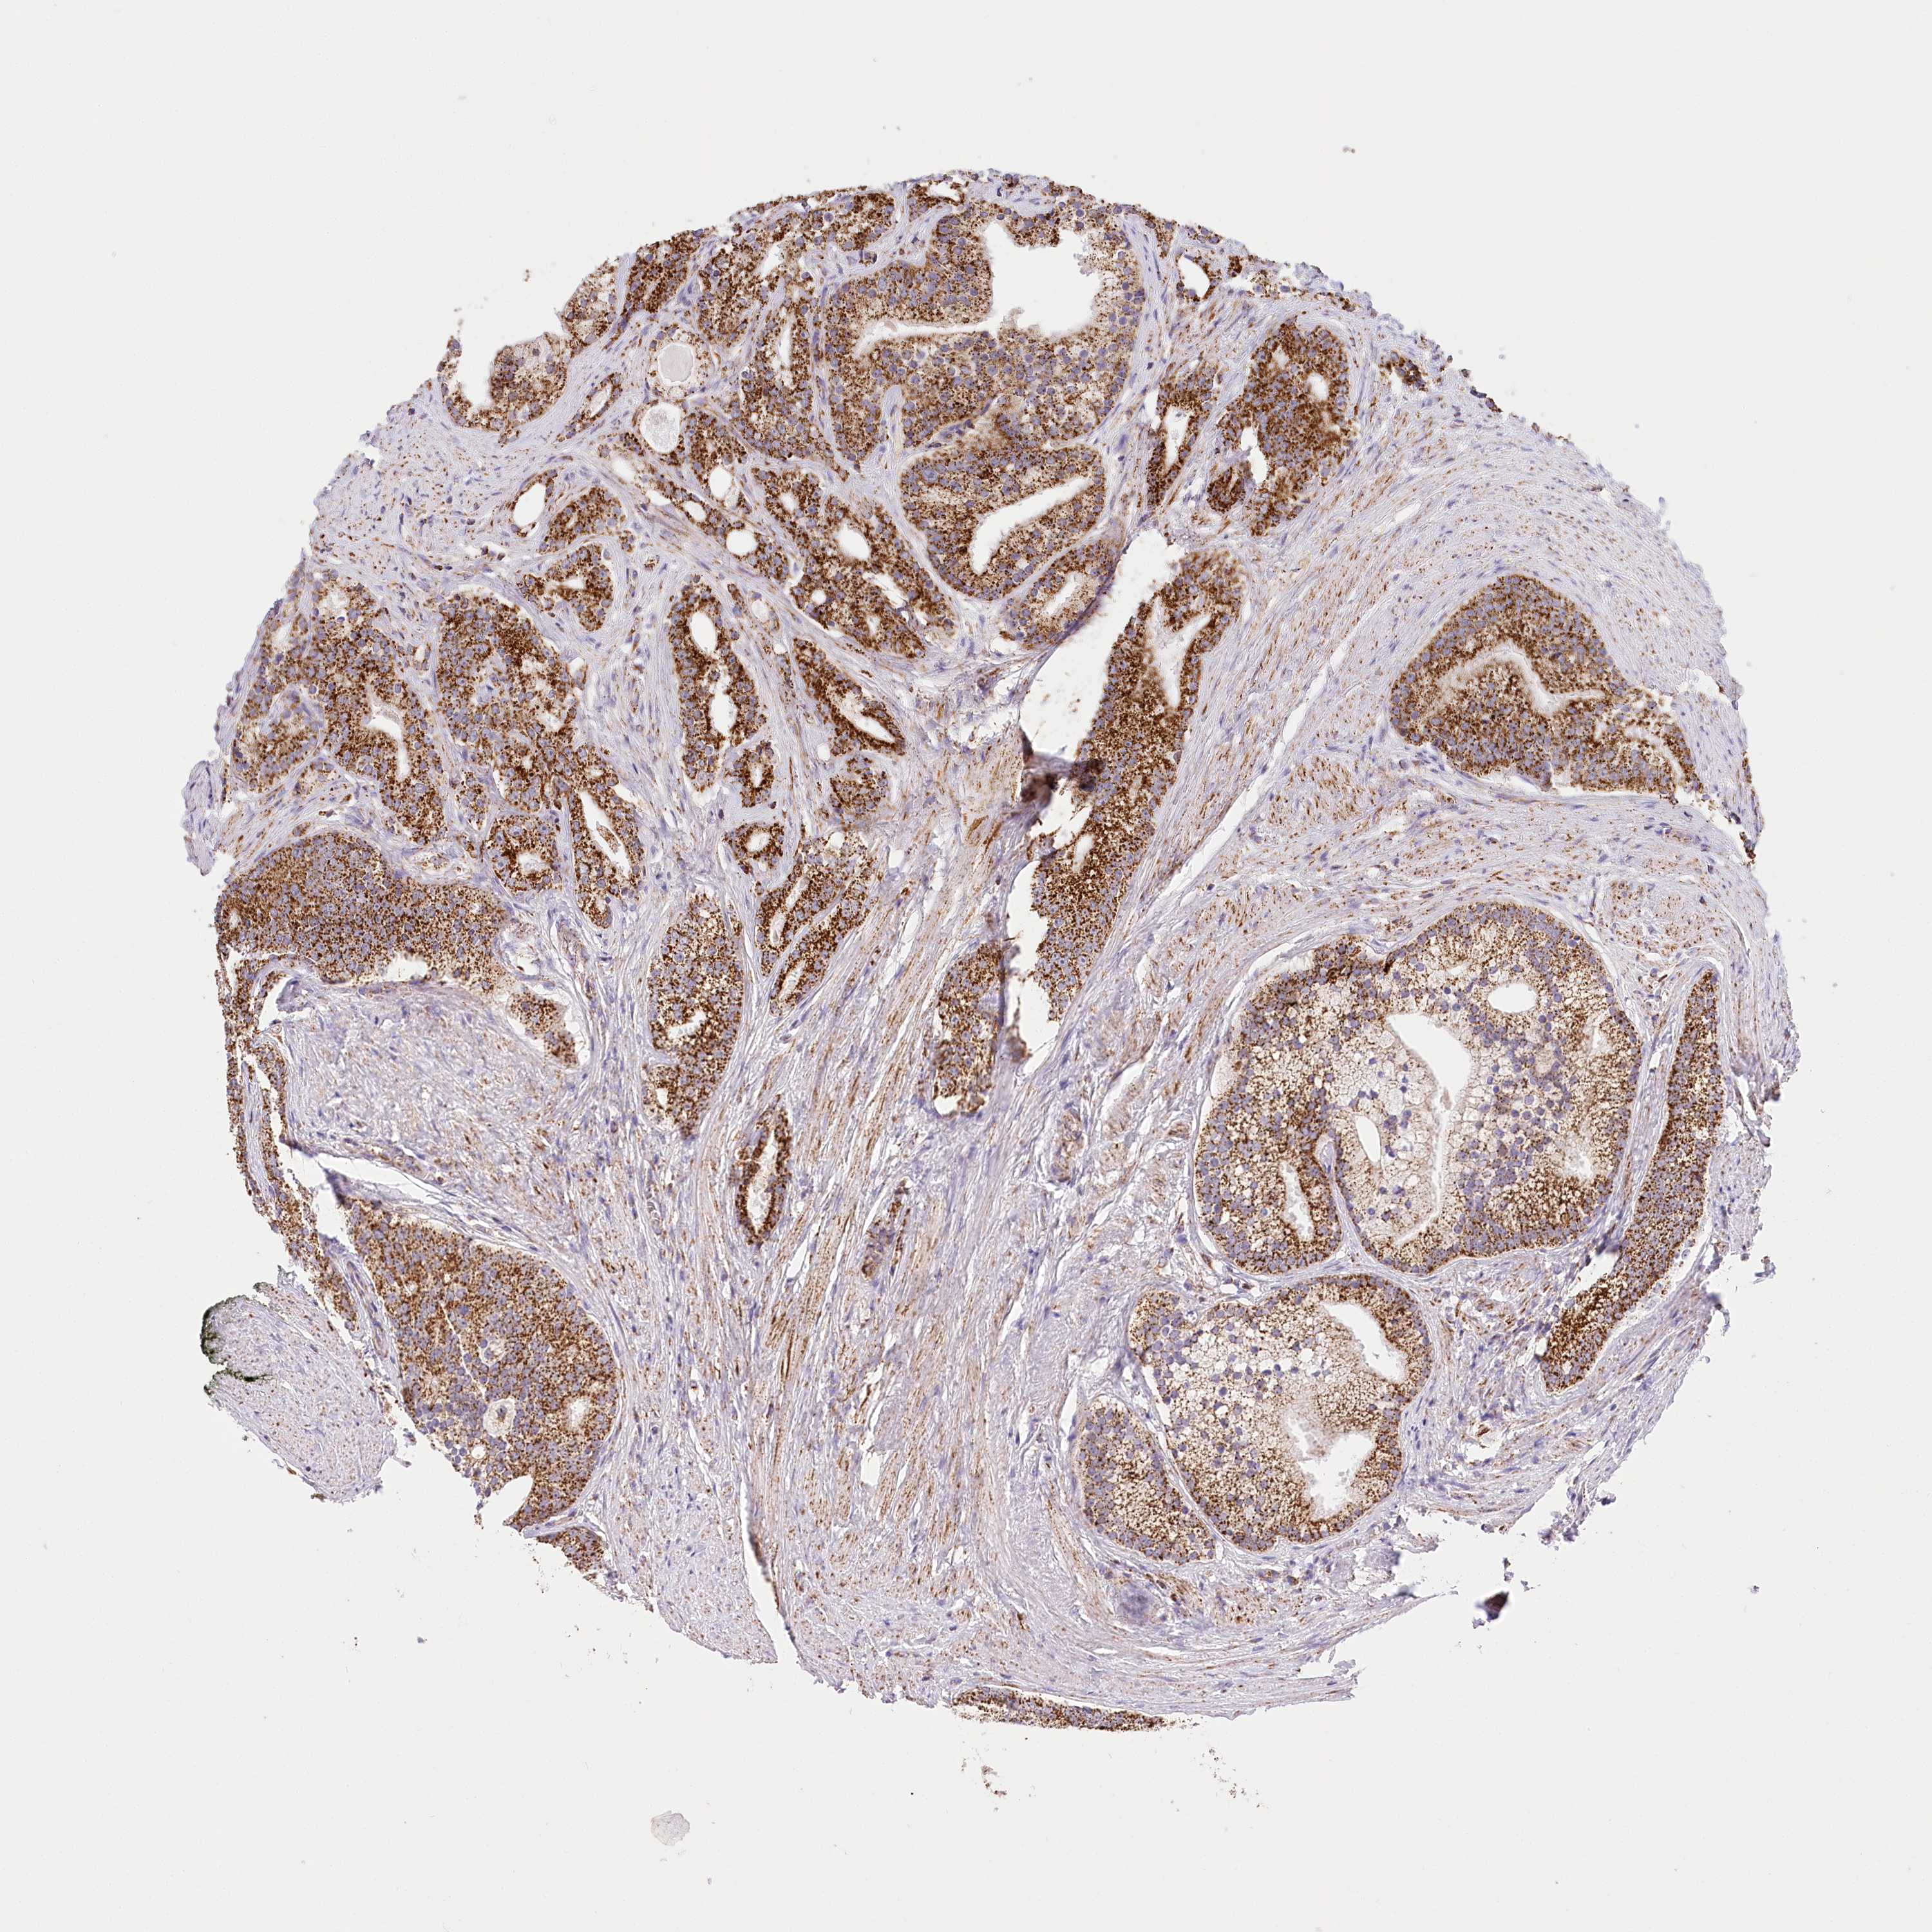

PROSTATE CANCER - Protein expressioni

A mouse-over function shows sample information and annotation data. Click on an image to view it in a full screen mode. Samples can be filtered based on level of antibody staining by selecting one or several of the following categories: high, medium, low and not detected. The assay and annotation is described here.

Antibody stainingi

Antibody staining in the annotated cell types in the current human tissue is reported as not detected, low, medium, or high, based on conventional immunohistochemistry profiling in selected tissues. This score is based on the combination of the staining intensity and fraction of stained cells.

Each image is clickable and will lead to virtual microscopy that enables deeper exploration of all samples and also displays staining intensity scores, fraction scores and subcellular localization as well as patient and tissue information for each sample.

Antibody HPA032060

Antibody HPA032062

Antibody CAB034116

Staining

High

Medium

Low

Not detected

Intensity

Strong

Moderate

Weak

Negative

Quantity

>75%

75%-25%

<25%

None

Location

Nuclear

Cytoplasmic/membranous

Cytoplasmic/membranous,nuclear

Adenocarcinoma, Low grade

Adenocarcinoma, High grade